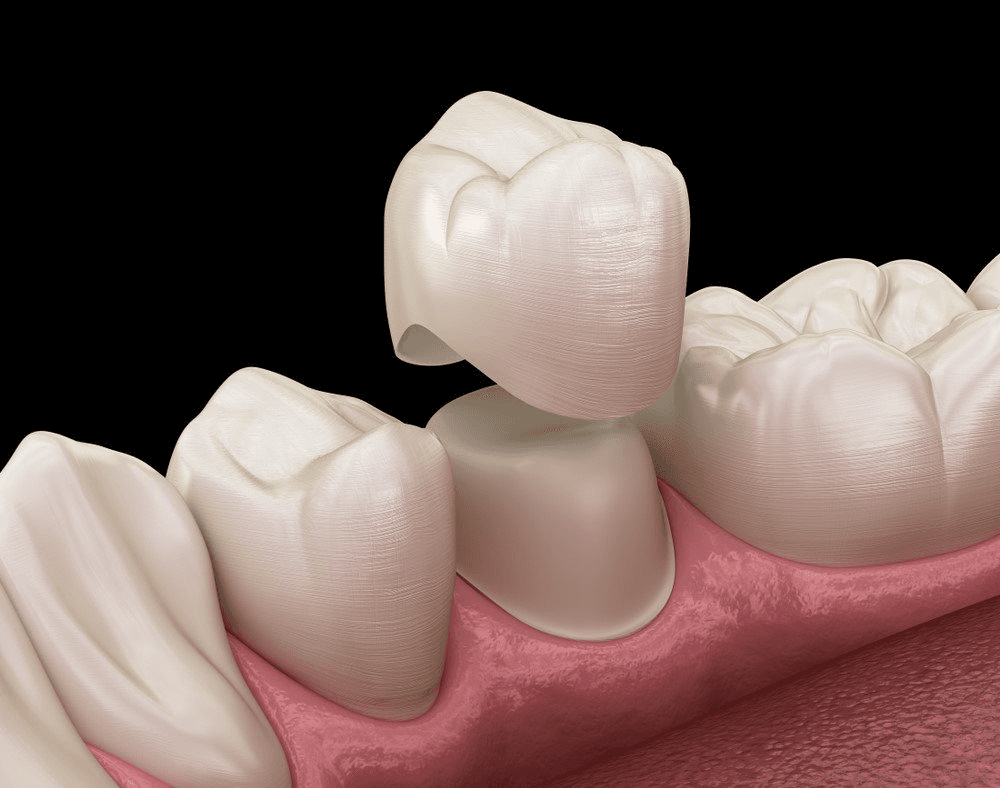

Dental Crowns

For teeth with extensive decay but a stable root structure, a dental crown provides protection and strength. A custom-made crown covers the damaged tooth, restoring function and appearance.